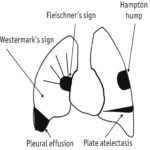

Dấu Hiệu X-Quang Ngực I Bài giảng CĐHA

Tài liệu tham khảo:

* Dấu hiệu X-Quang lồng ngực – Bs. Nguyễn Quý Khoáng

* Thực hành X-Quang ngực – TS. Nguyễn Văn Thành

* Bài giảng Chẩn đoán X-Quang – PGS.TS Phạm Ngọc Hoa

* Classic Signs in Thoracic Radiology – A. Manzella, P. Borba Filho, E. Marchiori

* Classic signs in thoracic computed tomography: a pictorial review – E. F. M. P. Negrao, B. S. D. Flor de Lima, J. Pinheiro Loureiro

* Signs in Thoracic Radiology : Role of radiographic signs in the present era – A. Mahajan; Mumbai/IN